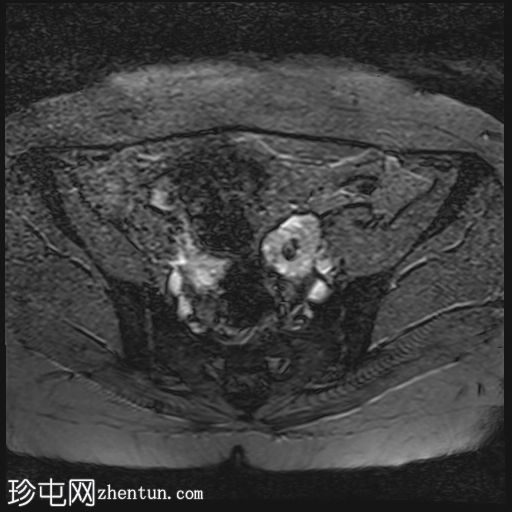

轴位

T2加权像

双侧卵巢位置接近(卵巢相吻),左侧卵巢内可见一边界清晰的囊性病变,大小约3.1 × 2.7 × 2.9 cm,T1加权像呈高信号,T2加权像可见暗点征及内部暗点征。以上MRI特征符合卵巢子宫内膜异位囊肿的诊断。

右侧卵巢可见一囊肿,大小约为 2.8 × 2.0 × 2.2 cm,T1 加权像呈高信号,囊内可见液-液平面,提示囊内含有不同时期的出血性物质。由于对侧卵巢存在典型的子宫内膜异位囊肿,且该囊肿无强化,影像学表现强烈提示为另一子宫内膜异位囊肿。

双侧卵巢囊性病变,MRI 表现符合子宫内膜异位囊肿的特征,左侧较大。未见强化壁结节或实性成分,提示无恶性转化。